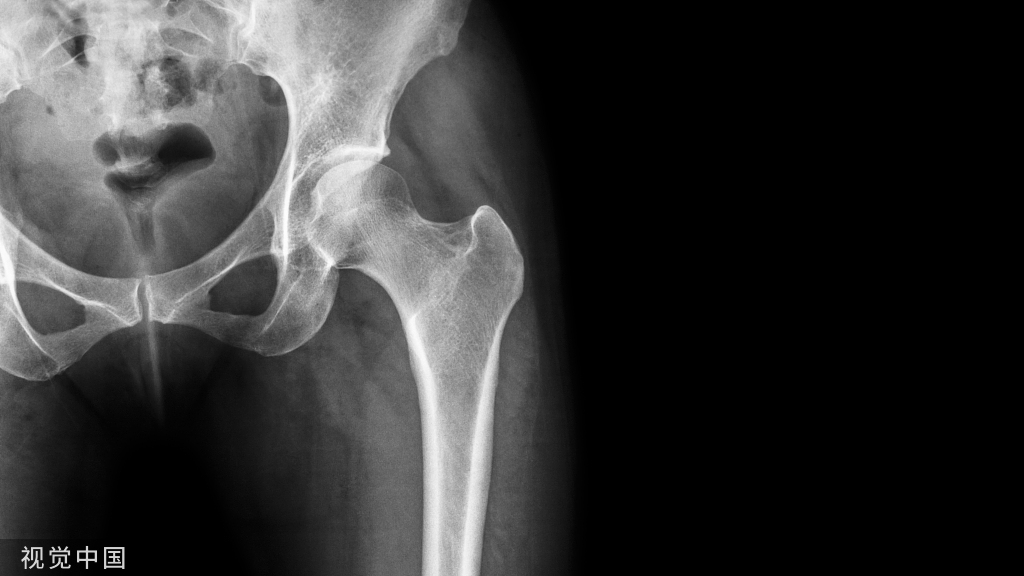

植入物取出后,胸片显示锁骨骨折完全愈合,随访1年,肩锁关节脱位保持良好复位